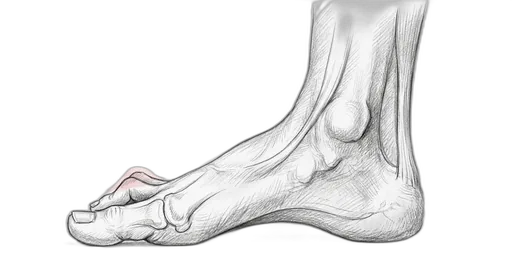

At a glance: A hammertoe is a contracture (permanent bend) of the small joints of the toes, most commonly the second toe. In the flexible stage, you can still straighten the toe by hand — and that's when exercises make the biggest difference. Once the joint becomes rigid, the deformity is fixed and typically needs surgical correction. The exercises here target the intrinsic foot muscles that extend the toes and counterbalance the flexor pull that causes the curling.

Understanding Hammertoe

The small toes work through a tug-of-war between the muscles on top of the foot (extensors) and the muscles underneath (flexors), coordinated by the small intrinsic muscles inside the foot. When the intrinsic muscles weaken — from wearing tight shoes, neurological conditions, or simply from years of disuse — the flexors win and the toes buckle at the proximal interphalangeal (PIP) joint. This creates a raised joint that rubs against the top of the shoe, forming a painful corn. Over time, the tendons and joint capsule tighten, and the flexible deformity becomes rigid. Hammertoes frequently accompany bunions because the big toe drifting sideways crowds the second toe upward.